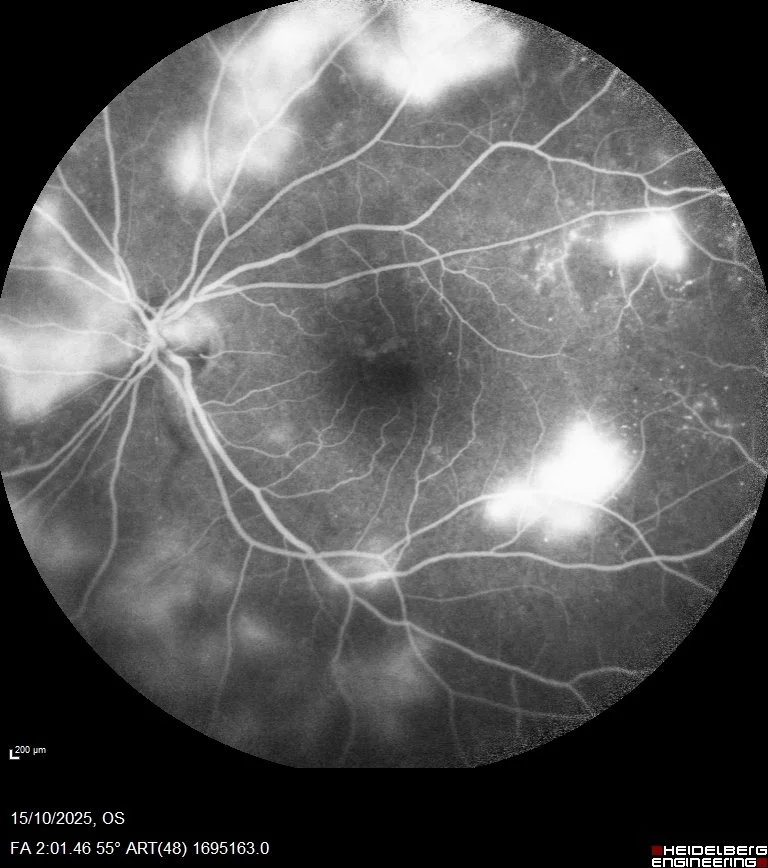

- Focal φωτοπηξία στις ισχαιμικές περιοχές, μετά από φλουοροαγγειογραφικό έλεγχο

- Panretinal φωτοπηξία (PRP) όταν υπάρχει παραγωγική αμφιβληστροειδοπάθεια

Τι περιλαμβάνει ο έλεγχος: Βυθοσκόπηση με μυδρίαση — OCT για ανίχνευση οιδήματος ωχράς — Σε ορισμένες περιπτώσεις: Angio-OCT ή φλουοροαγγειογραφία